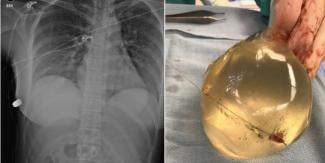

Η ακτινογραφία του στήθους της 30χρονης γυναίκας

Η σφαίρα μπήκε από το αριστερό στήθος και κατέληξε στο δεξί

Μέσω ακτινογραφιών, οι γιατροί μπόρεσαν να εντοπίσουν την σφαίρα στο δεξί πλευρικό θωρακικό τοίχωμα, ένα σπασμένο πλευρό και φυσαλίδες αέρα στο αριστερό στήθος και κατέληξαν στο συμπέρασμα πως η σφαίρα ταξίδεψε από το αριστερό στήθος στο δεξί θωρακικό τοίχωμα. Οι γιατροί φυσικά, αφαίρεσαν τα εμφυτεύματα ενώ συνταγογράφησαν αντιβιοτικά, κλείνει η έκθεση.